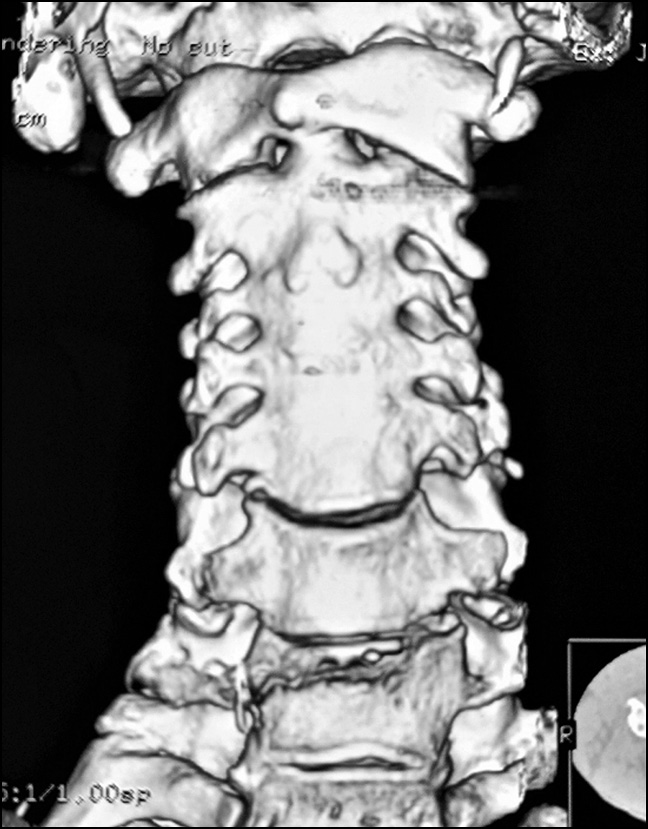

Control radiographs revealed multiple heterotopic ossifications of the axial and peripheral skeleton and submandibular region and multiplanar spinal deformity (Figs. 1–3). Computed tomography revealed synostosis of the 2nd–5th cervical vertebrae, which exhibited fusion of not only their posterior elements but also their bodies (Figs. 4 and 5). Synovial chondromatosis, one of the most common manifestations of FOP, was identified during a hip joint examination (Fig. 6). In addition to intra-articular chondromal bodies, heterotopic ossifications in the hip joints completely inhibit the movements in this skeletal region and significantly impeded walking (Figs. 7 and 8).

Fig. 5. Three-dimensional CT reconstruction of the cervical spine, anterior view: synostosis of the C2-C5 vertebrae.